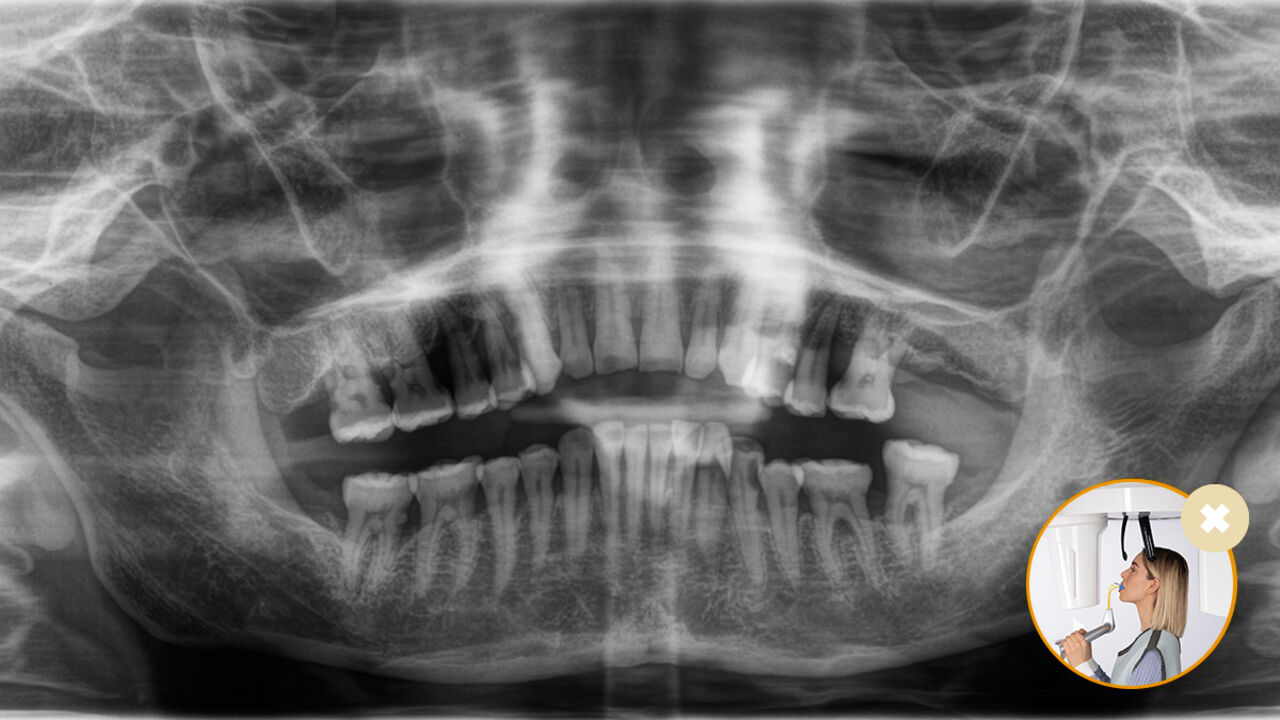

Correct patient positioning leads to high image quality to support an accurate diagnosis and facilitates and improves patient experience.

This is our 10-point concept for easy patient positioning and X-ray imaging. It is primarily about two things: high image quality and comfort for the patient and the assistant.